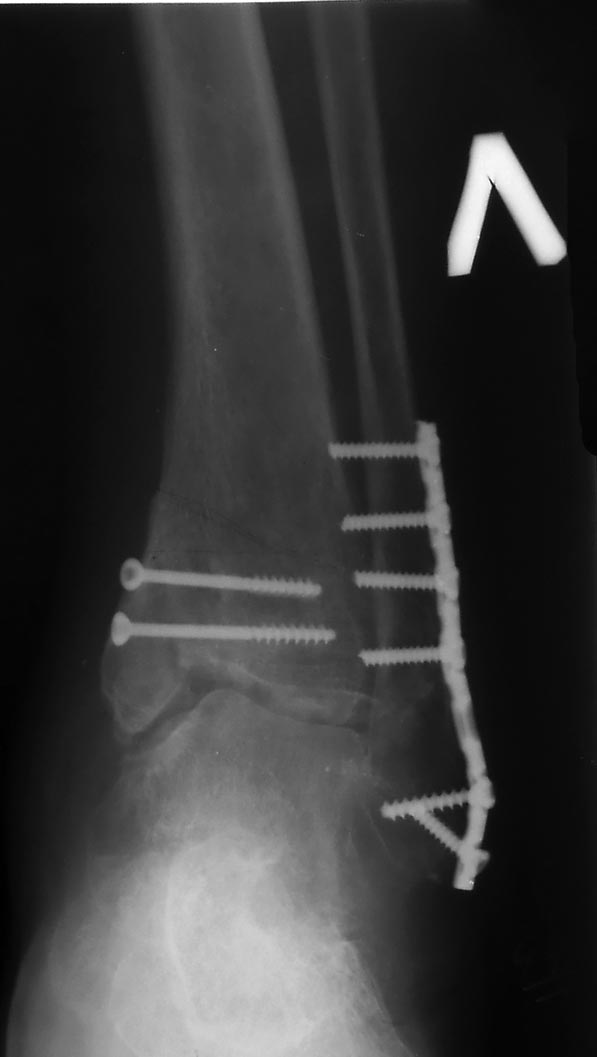

К чему приводит остеосинтез разными металлами...

Женщина 1953 г.р., в январе 2011 года остеосинтез титановой пластиной и

стальными винтами... Что делать ????